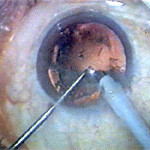

CATARACTOUS LENS BEING BROKEN BY PHACO NEEDLE THROUGH

1 MM to 2.8 MM IN INCISION